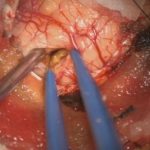

症例 '25年10月

No.

673

小脳腫瘍

頭蓋内腫瘍摘出術

術中写真

摘出 中